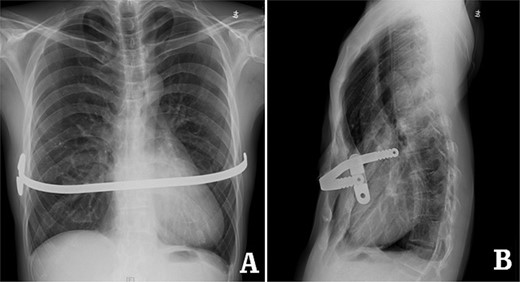

examination showed that the anterior chest wall was sunken and uneven in the middle, and two scars were visible on the lateral chest wall (Fig. 1). The preoperative imaging examination showed that there was a steel bar in the chest wall, and the anterior chest wall was depressed. The lower part of the sternum was broken, with its distal end was supported up by the steel bar. The lower end of the sternum was located deep beneath the steel bar, and the heart was obviously compressed (Figs 2–5). The operation was performed under general anesthesia. Incisions were made in the middle of the depression and two sides of chest wall. After the steel bar was taken out, the adhesion behind the sternum was separated through the median incision. Wung procedure was performed with two steel bars to support the depressed lower part of sternum [4], and then, the third steel bar was used to perform Wenlin procedure to flatten the protrusion part of the rib arch [5, 6] (Figs 6 and 7). During the two procedures, Wang technique was used to fix all the steel bars [7]. After the two procedures were completed, drainage tubes were placed in bilateral thoracic cavities and median surgical field, and the incision was closed to end the operation (Fig. 8). The operation time was 90 min, and the operation was smooth without any complications. The appearance of chest wall returned to normal after the operation, and imaging examination showed that the position of steel bars was satisfactory (Figs 8 and 9). The patient was discharged 7 days after operation.

Computed tomography examination before operation. (A) Coronal view; (B) sectional view; and (C) sagittal view.